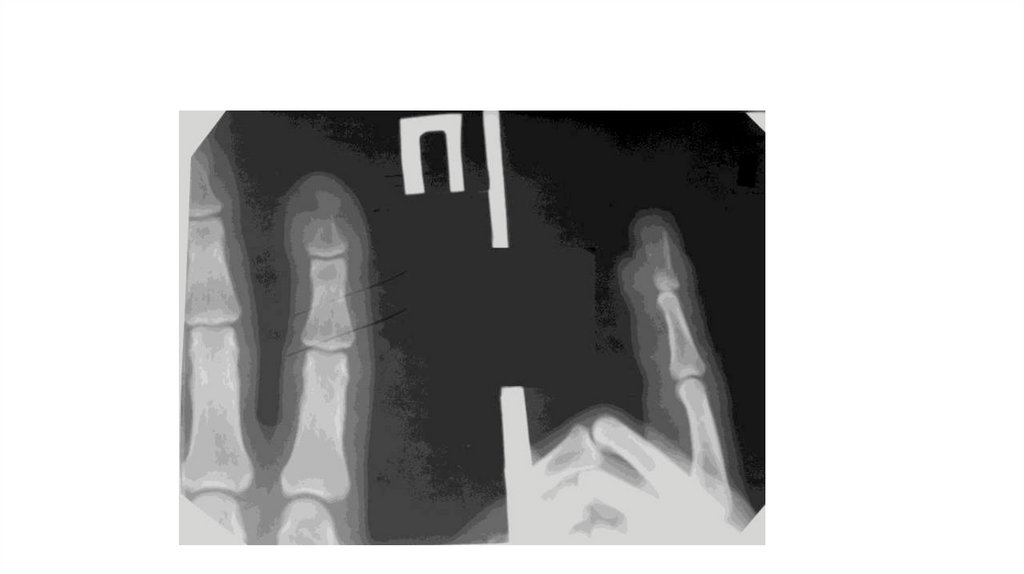

Воспалительные заболевания опорнодвигательного аппарата

«Воспалительные

заболевания опорнодвигательного аппарата»